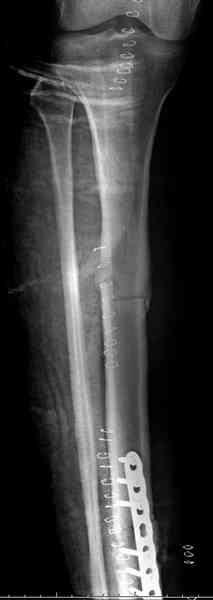

"При его рассмотрении с рентгенологом и морфологом сошлись, что это не фиброзная дисплазия, что было первым предположением по рентгенограммам. В полости было и мягкотканое образование. Окончательно заключение дадут через несколько дней"

По локализации и по характреру опухоли мало напоминает остеобластому, может, представленные биопсийные материалы адамантиномы помогут вашим морфологам дифференцировать опухоль (Basiloid cells, pseudoglandular pattern and peripheral palisading)

Недавно на нашей ежемесячной Morbidity&Mortality

conference мы разбирали похожий случай, ложный сустав большеберцовой кости после резекции опухоли.

К нашему онкологу-ортопеду обратился больной с жалобами на боли в голени, из рассказа - год назад была сделана биопсия большеберцовой кости, но название заболевания "не запомнил”.

Оперирован в военном госпитале с заменой сегмента

аллокостью большеберцовой кости и после демобилизации явился для постоянного наблюдения по месту жительства.

В литературе "A Classic Adamantinoma Arising from

Osteofibrous Displasialike Adamantinoma in the Lower Leg: A case report and Review of the Literature похожие снимки.

Наши имели проблему со сращением, пришлось им сделать динамизацию, дополнительную аутопластику.

Снимки представлены.